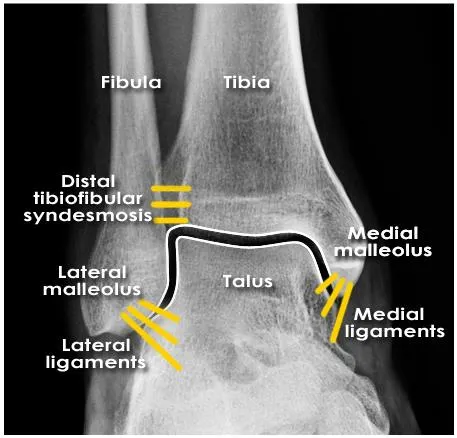

Ankle bone and lig. anatomy

Not visible

Joint space

understanding of the anatomical position of ligaments is required to appreciate the presence of ligament injuries

Ankle anatomy (Lig.)

Syndesmotic ligament complex

Deltoid (medial) ligament complex

Lateral (fibular collateral) ligament complex